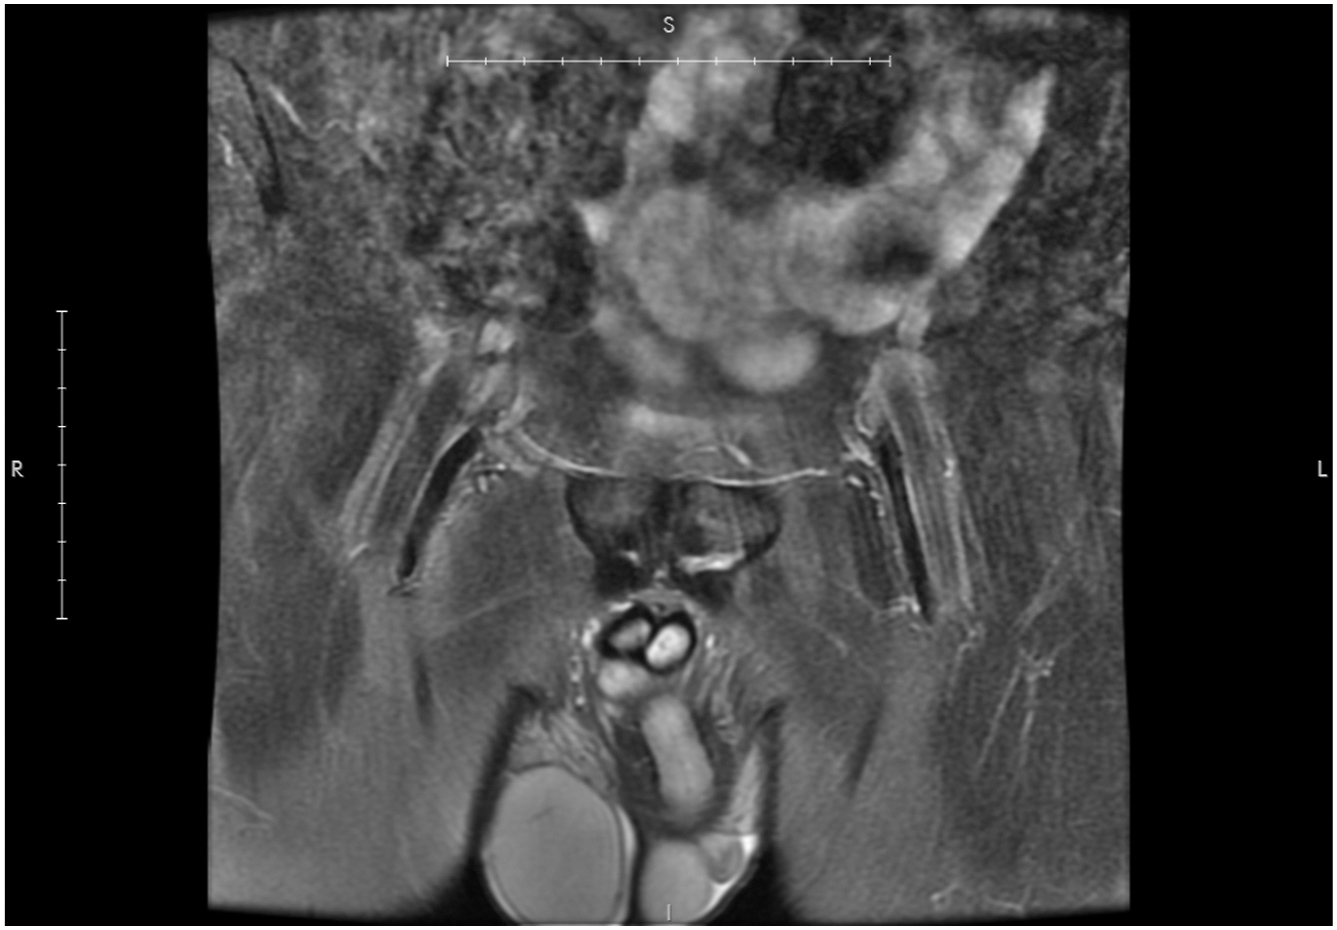

Because ultrasound is relatively inexpensive and widely available, it is often an appropriate next step. The presence of edema around the pubic bone or along the surrounding musculature, or signs of atrophy or laxity of the abdominal wall should prompt one to get an MRI with the “athletic pubalgia” or Jefferson protocol to better define the muscles involved.

The authors place primary importance on the presence of fluid between the pubic bone and the overlying fibrocartilage plate ( Fig. 1 ). The presence of peri-pubic and bone marrow edema (osteitis pubis) is a secondary sign of injury and it should raise one’s suspicion for a plate detachment. It is important to recognize that in skeletally immature patients, the fluid can be present along the growth plate (ie, subphyseal, Fig. 2 ). This has been referred to as a “secondary cleft” and can easily be overlooked. Chronic plate detachments ( Fig. 3 ) can also be more difficult, occurring in long-standing injuries where spicules of granulation tissue fill in portions of the gap between the fibrocartilage plate and pubic bone. Degenerative plate detachments have a similar appearance but the edges of the fibrocartilage develop a lytic appearance, and the authors think these occur with repetitive trauma ( Fig. 4 ). It is also important to keep in mind that conventional Mendelian randomisation (MR) studies of the pelvis or hip are often read as normal ( Fig. 5 ) or as showing some nonspecific changes of the pubic symphysis or edema patterns, leading to incorrect diagnoses, such as stress fracture or even worse, no injury.